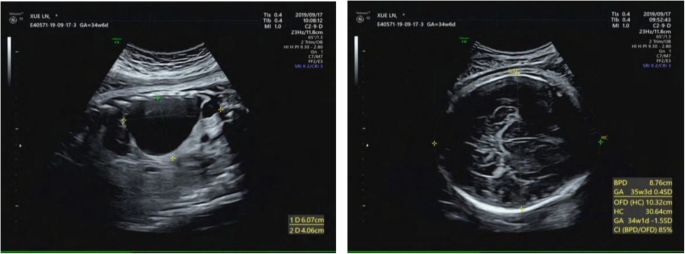

The abnormality was judged as consistent with a macrocystic congenital cystic adenomatoid malformation of the lung situated in the left lower thoracic cavity, and this abnormality led to a significant shift of the mediastinal structures to the right side. Repeated ultrasound scans during pregnancy showed that the malformation grew (Figs. 2, 3).